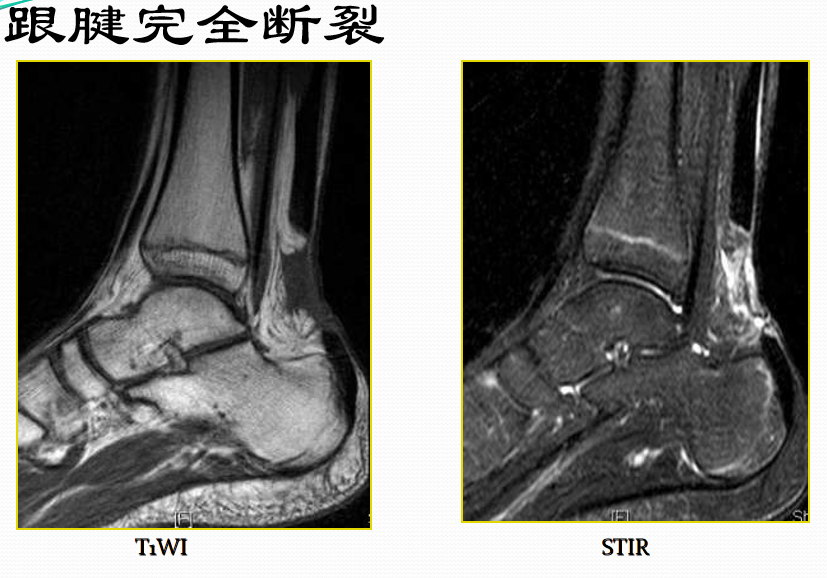

跟腱断裂

病因病理机制:

• 有体育运动史,对抗收缩力的足被动背屈(小腿三头肌群)

• 常位于跟骨上方2~6cm处发生断裂

• 类风湿性关节炎、系统性红斑狼疮、糖尿病和痛风

• 急性断裂:易患因素包括慢性跟腱炎和部分撕裂

MR表现:(信号+形态)

• 正常跟腱呈均匀低信号

• 脂肪抑制T2WI图像上,跟腱内部或跟腱周围软组织出血或水肿表现为信号增高,跟腱断裂/撕裂表现为跟腱连续性中断或波浪状回缩

• 跟腱近端回缩,跟腱边缘磨损,呈螺旋状形态

• 撕裂处增粗的近端与远端之间可见疏松的连接